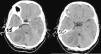

Presentamos el caso de una mujer de 52 años, sin antecedentes de interés, que fue derivada a nuestro centro tras ser diagnosticada de una lesión ocupante de espacio en el hemisferio cerebeloso derecho. La sospecha inicial era de metástasis. En la RMN cerebral, sin embargo, se apreciaba una marcada restricción en la secuencia de difusión concordante con un absceso cerebeloso. La paciente se había sometido a una limpieza dental tres semanas antes. El análisis microbiológico tras la evacuación quirúrgica de la lesión mostró la presencia de Streptococcus intermedius.

A 52-year-old woman with no relevant previous medical history was diagnosticated of an infratentorial bulky cerebellar mass. The mass showed restricted diffusion on MR images, which was consistent with cerebellar abscess. The patient had undergone a minor dental procedure three weeks before. Microbiological analysis after surgical evacuation of the mass confirmed the presence of Streptococcus intermedius.